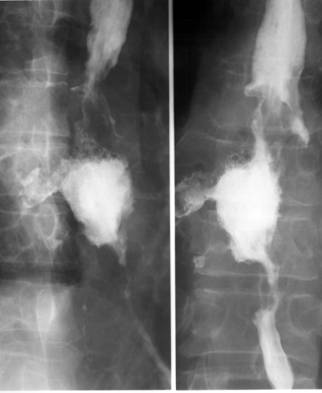

Fig. 40 – Tumora esofagiana maligna mixta (stenoza excentrica cu margini neregulate, imprecise continuata spre lumenul esofagian prin imagini lacunare si semitonuri marginale)

- cancerul vegetant – se manifesta radiologic prin aparitia lacunelor, unice sau multiple, cu aspect policiclic, neregulat, imprecis conturate, continuate deseori spre periferie cu imagini de semiton. La marginea imaginii lacunare se pot observa “pinteni maligni”, produsi de insinuarea contrastului intre baza tumorii si peretele esofagian. In proiectie marginala, formatiunea produce o ingustare excentrica a lumenului, care evolueaza spre stenoza. Uneori, lacuna are un aspect neomogen prin prezenta unor imagini opace neregulate care traduc ulceratii ale tumorii. Pliurile mucoasei esofagiene sunt intrerupte in zona afectata.